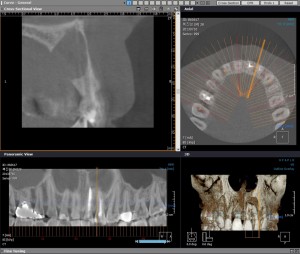

2013-07-15 CT

그런데 신경치료 후에도 염증의 사이즈가 줄어들지 않아서 치근단수술을 진행하기로 하였습니다.  정확한 진단을 하기 위해서 CT를 찍어 보았습니다.

치근단 수술 이란 신경치료만으로 회복되지 않을 때 외과적 처리를 병행함으로써 치아를 보존시키는 술식입니다. 치근의 끝 부이에 있는 치조골 주변의 염증조직을 치근단과 같이 제거하게 됩니다. 잘라낸 치아 뿌리에는 MTA(Mineral Trioxide Aggregate)를 사용하여 손상된 신경부위가 치유되게 합니다.

환자분의 경우는 잇몸뼈도 많이 없어져 있기에 뼈이식도 함께 진행하기로 하였습니다.